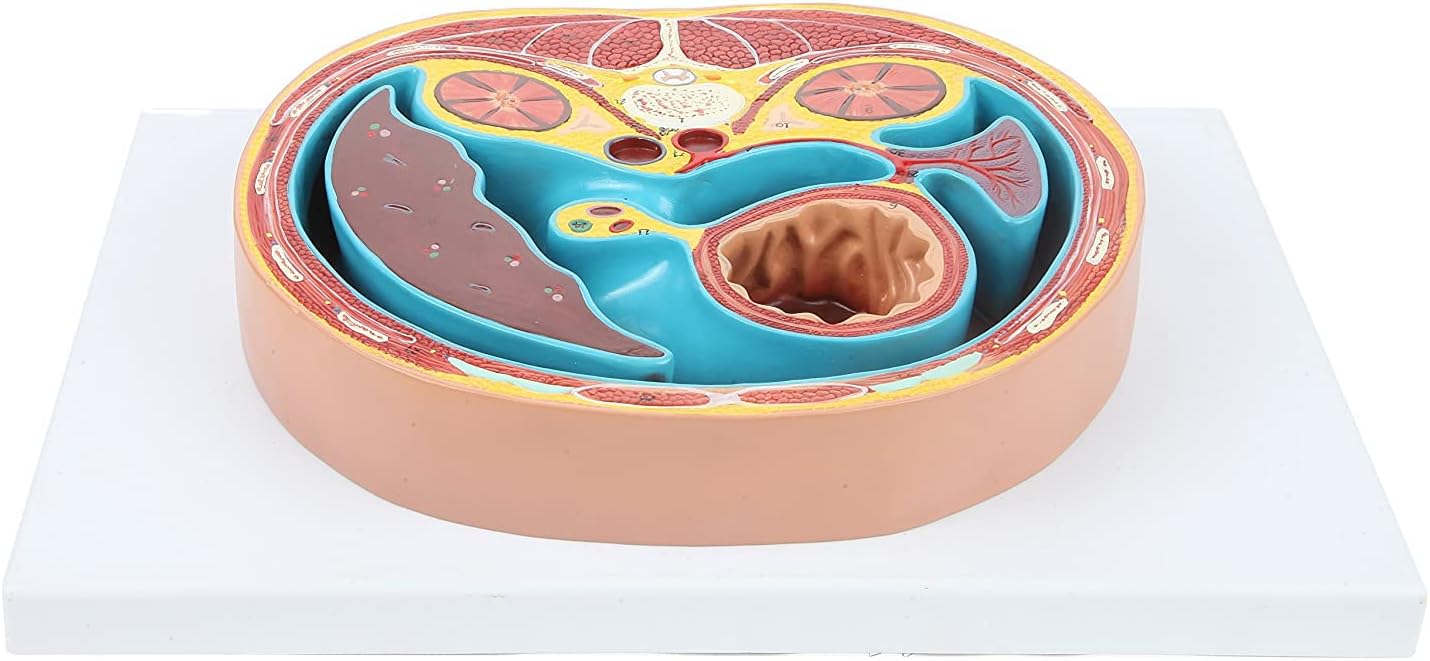

The cross-sectional model of the thoracic cavity shows about the height of the T8 lumbar vertebra.

Size: 31*21*4cm

Applicable To:Applicable to schools,hospital, in physical health teaching, can be used as a teaching of physical health knowledge of the visual aids, so as to deepen the understanding of the structure of the human thoracic cavity.

Anatomical Standard:According to the normal anatomical posture, the flat mediastinum is used as a cross-cut design, and the height of the eighth thoracic vertebra is shown in detail.